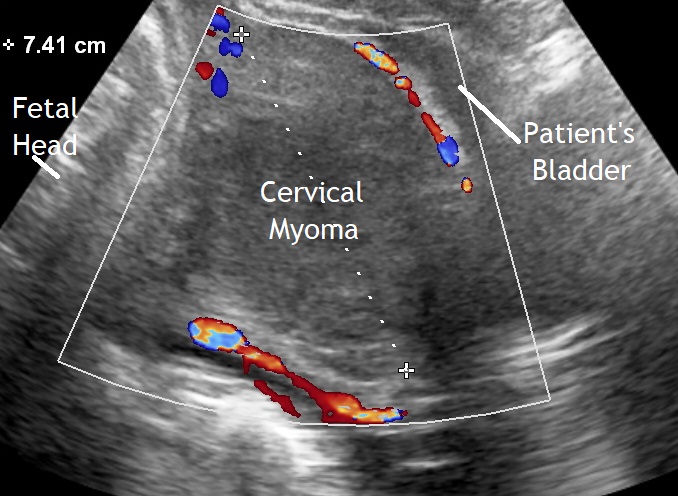

Our first image shows a cercical myoma with a diameter of 7 cm. Cesarean section was performed.